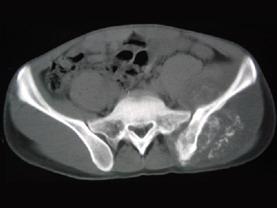

问题 男,35岁,左髂部剧烈疼痛,尤以夜间明显,可摸到肿物,请结合所提供图像,选择最佳选项 ( )

选项 A、骨肉瘤 B、软骨瘤 C、软骨肉瘤 D、骨转移瘤 E、骨巨细胞瘤

答案 A